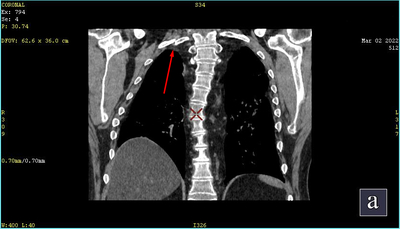

Меня собирают, грузят обратно на каталку и минуя приёмный покой везут сначала на КТ, а потом сразу в реанимацию (ОРИТ). Врачи больницы, делавшие КТ, видят 64% поражения лёгких и «отсутствие деструктивных и травматических изменений костей в зоне сканирования». Потом неделя медикаментозной комы, нИВЛ, после прон-позиция на правом боку и животе, 18 дней в самом ОРИТе. Ещё одно КТ — снова без «деструктивных и травматических изменений костей».

23.02.23 я обратился в центр им. Алмазова, где в рамках услуги «Второе мнение» мне описали два диска с КТ из больницы Св. Георгия, по которым были вопросы. Напомню, первое КТ было при поступлении в больницу, спустя 3-5 минут после травмы (мне кажется, оно может рассчитывать на призовое место в списке «Самое быстрое КТ в России»), второе через 18 дней при переводе из ОРИТ в палату отделения терапии. Результаты были — огонь.

На первом диске переломы ключицы и 1, 3, 5, 6, 7, 8-го рёбер с правой стороны.

На втором: то что было в первом + смещение отломков 1-го ребра, два перелома 2-го ребра, перелом 3-го ребра и два перелома 4-го ребра. Часть со смещением, часть нет. Итого 7 переломов при падении + 5 переломов в реанимации. Суммарно 12 переломов костей: ключица и восемь рёбер (из них три перелома двойные)